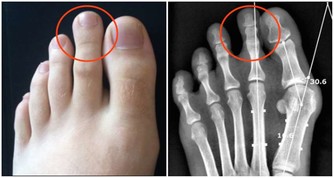

當人們長期性的走路久時,下肢靜脈壓力相應的較低,下肢靜脈,淋巴液回流受阻,從而引起膝蓋酸腫,因而走路久了需要休息。如果長期性走路久了引起膝蓋酸痛,就需要到正規的醫院對膝蓋部位做x光片檢查骨質情況,再聽醫生的話進行治療。